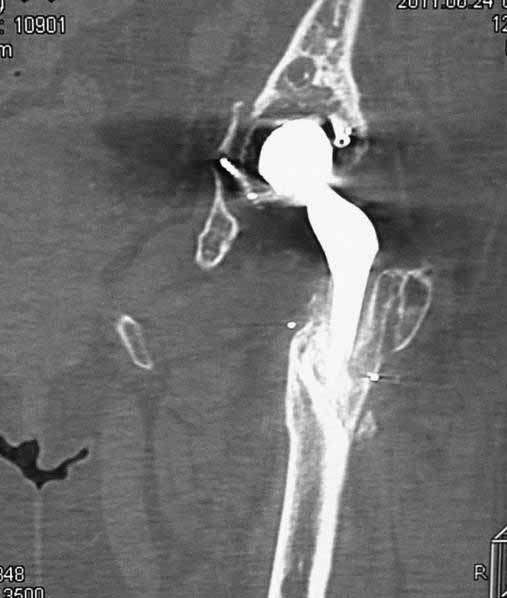

Уважаемые коллеги. Хотелось бы услышать мнения и советы по представляемому случаю.

Пациентка 45 лет. Бесцементное эндопротезирование левого тазобедренного сустава 6 лет

назад (впадина RM, Mathys, металл-металл, ножка Зульцеровская). За 10 лет до

протезирования коррегирующая остеотомия бедренной кости, которая не срослась в течение

года до удаления пластины, а затем срослась в течение 3 месяцев иммобилизации в кокситной

повязке. После протезирования получилось наблюдать пациентку почти постоянно, поскольку

через 2 года синтезировал ей лодыжки на оперированной стороне, затем, через несколько

месяцев удалил фиксаторы, а в 2009г. резецировал мениск на противоположной стороне. Боли

все эти годы не беспокоили. Пациентка чуть выше среднего роста, вес тела нормальный.

Физические нагрузки переносила хорошо. Работает на 7 этаже без лифта. Год назад экстирпация

матки по поводу лейомиомы больших размеров. Несколько месяцев назад появились боли в

области левого тазобедренного сустава. При рентгеновском и КТ исследованиях (июль с.г.)

нестабильность тазового компонента. От предложенной замены протеза пациентка на тот

момент, слава богу, отказалась. Через какое то время боли в области левого тазобедренного

сустава практически полностью прошли, а около 2 месяцев назад появилось ощущение

патологической подвижности таза и боли в паху справа, которые через некоторое время

уменьшились, а потом снова усилились после значительных физических нагрузок (много ходила

по песку на пляже, носила тяжести). Ежедневно принимала диклофенак. На рентгенограммах

переломы правой лонной кости. Сейчас госпитализирована из-за болей в паху справа. Боли

слева не беспокоят. На фоне снижения нагрузок в стационаре боли значимо уменьшились.

-Если думать о ревизии, то когда? На представленных снимках тазобедренный сустав до и

сразу после операции, затем 2 снимка 2009г., когда ничего не беспокоило, затем КТ 2-х

месячной давности и вчерашние рентгенограммы обоих тазобедренных суставов.